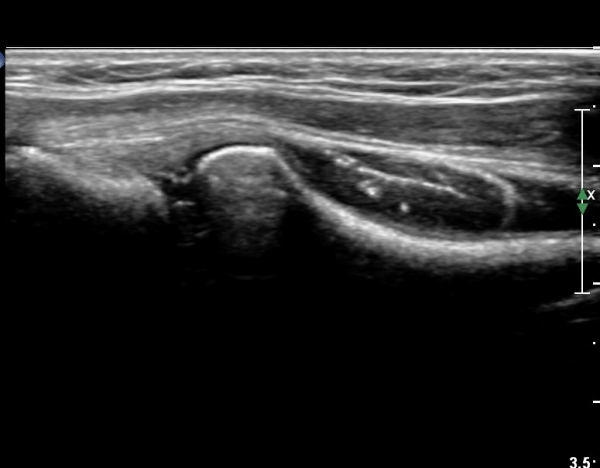

ŽÃÊÀÚ¸¦¸»´ÜÀ¸·Î  À̵¿ÇÏ´Ï ¿ä°ñ¸ñ ºÎÀ§¿¡¼­ Ä¿´Ù¶õ ³¶Á¾ÀÌ Èİñ°£ ½Å°æÀ» ¾Ð¹ÚÇÏ´Â °ÍÀÌ

°üÂûµÈ´Ù(»çÁø 4, 5)

Á¶±Ý´õ ŽÃËÀÚ¸¦ ¸»´ÜÀ¸·Î À̵¿ÇÏ´Ï ³¶Á¾Àº ÀÛ¾ÆÁö°í ȸ¿Ü±Ù »çÀÌ¿¡ À§Ä¡ÇÏ´Â Èİñ°£ ½Å°æÀÇ

ºÎÁ¾ÀÌ °üÂûµÈ´Ù(»çÁø 6)